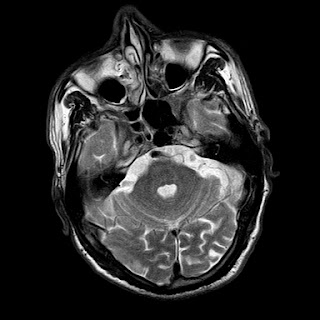

A 55 years old man with....